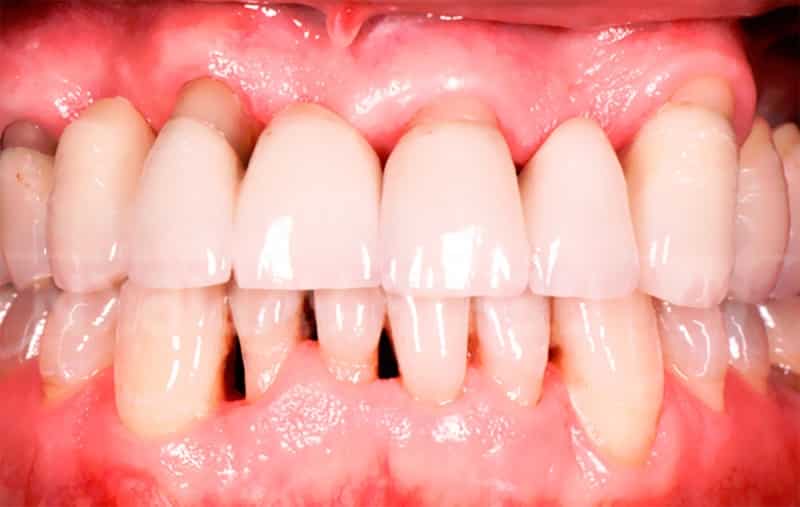

Для отличия пародонтоза от пародонтита существует несколько признаков. Во-первых, пародонтоз является редким заболеванием, в то время как пародонтит распространен. Во-вторых, причиной пародонтоза является нарушение клеточного питания, в то время как пародонтит связан с плохой микрофлорой ротовой полости и наличием зубных отложений. В-третьих, пародонтоз затрагивает альвеолярные отростки всей полости рта, тогда как пародонтит может быть локализованным или распространяться на несколько десен. В-четвертых, при пародонтозе отсутствует воспаление десен, а главным процессом является атрофия, в то время как при пародонтите преобладает воспаление. В-пятых, пародонтоз не сопровождается абсцессами, гнойными выделениями, кровотечениями и патологическими зубодесневыми карманами, в отличие от пародонтита. И, наконец, при пародонтозе зубы начинают расшатываться постепенно, с течением времени, в то время как при пародонтите расшатывание зубов происходит уже на ранних стадиях заболевания.

Пародонтоз можно классифицировать по нескольким показателям. Во-первых, по месту расположения он может быть генерализованным, когда затронуты обе челюсти или весь зубной ряд, или локализованным, когда атрофия наблюдается только на небольшом участке. Во-вторых, по активности дегенеративных процессов он может быть хроническим или острым. И, наконец, в зависимости от степени повреждений костной ткани выделяются пять стадий развития болезни: начальная, первая, вторая, третья и четвертая стадии.